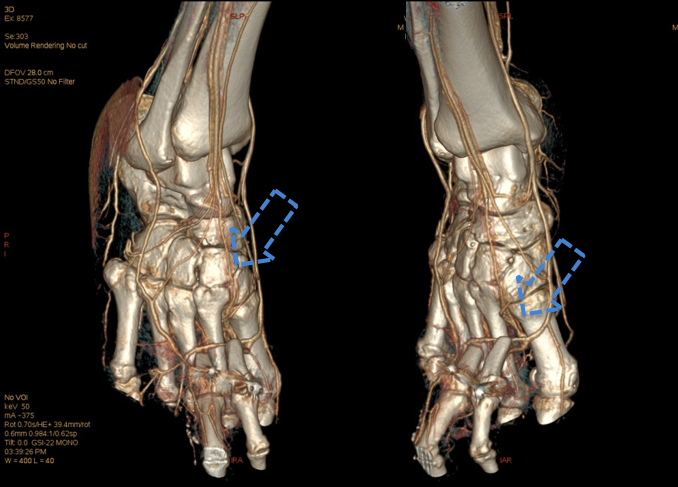

右足寄养皮瓣血管状况

选择50keV进行寄养动脉观察